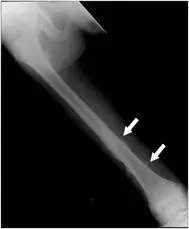

13 歲男國中生最近覺得右腳膝蓋附近偶爾隱隱作痛,且疼痛的時間越來越長,晚上睡覺時症狀也很明顯,附圖為下肢 X光攝影,最可能的診斷為何?

– X光顯示下肢長骨(應為遠端股骨或近端脛骨)骨幹處可見不規則的骨質透亮及高密度混合區,病灶邊緣模糊,骨皮質明顯隆起且新生骨呈放射狀及分層/中斷狀(aggressive periosteal reaction),部分區域可見類似 Codman 三角的骨膜抬舉,並伴有皮質破壞。

– 骨質新生分布不均,呈雲霧狀(osteoid matrix)的高密度模糊區。整體具有寬闊交界帶(wide zone of transition)與潰爛式(permeative/moth-eaten)破壞特徵,提示高度惡性病變。